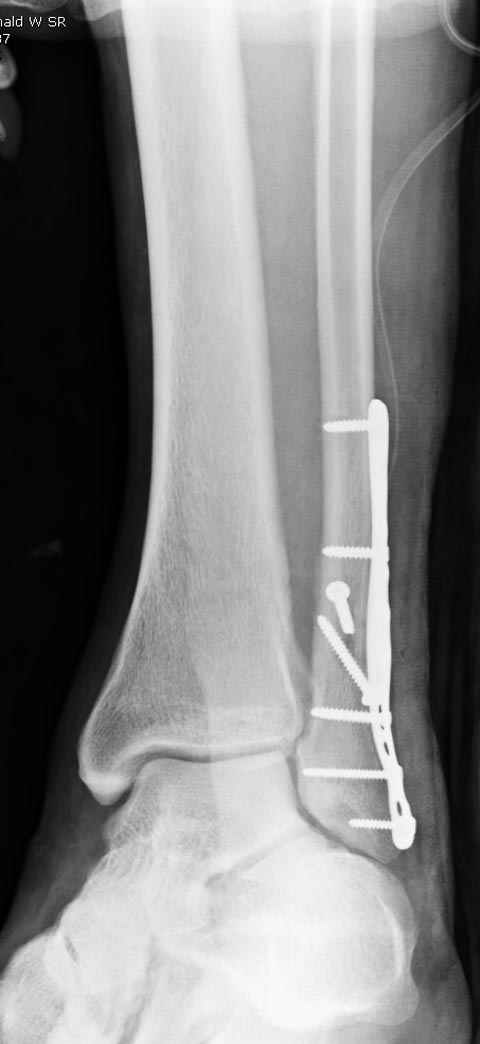

По снимку ваш случай относится к Weber В, фиксацию производят восстановлением длины малоберцовой кости, под ренгеном (ЭП)контролем, для этого я предпочел бы латеральный доступ, остеотомия по линии перелома, удлинение малоберцовой засчет скоса линии остеотомии, компрессия “lag technique”по линии остеотомии и фиксацию провести латеральной пластиной. Отдельный задний доступ, остеотомия по линии перелома, репозиция и фиксация заднего края вашим предпочтительным методом: 3.5мм шурупом с шайбой или пластиной Antiglide Butress

method. При восстановленном суставе, уменьшится медиальная щель, а при Weber В повреждается только передне-нижняя межберцовая связка синдесмоза, повреждение которой приводит к наружной ротации

малоберцовой, но после восстановления всех смещений, связка автоматический приближается к исходному и нет необходимости восстановления синдесмоза.